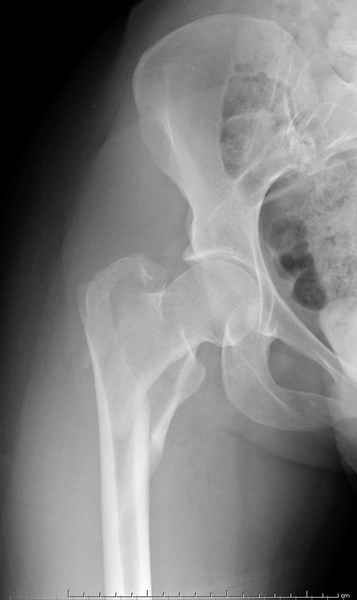

Для молодых больных выбрал бы тактику fixed angled device 95 degree Blade Plate, техника непрямого метода репозиции, который описал в своей книге Jeff Mast, Planning and Reduction Technique in Fracture Surgery ( method of Inderect Reduction), репозиция и фиксация происходит за счет фиксации головки бедра к femoral shaft с помощью пластины, а что в середине должны репонироваться без больших усилии и без разрушения мягкотканого соединения c медиальной стороны.

Пластина дает свободу:

Valgus-varus; extention- flexion, зависит только от образования канала для blade на головке.

Ap pelvis Rt sub-intra trochanteric Fracture, AP Rt hip, Postop Blade Fixation